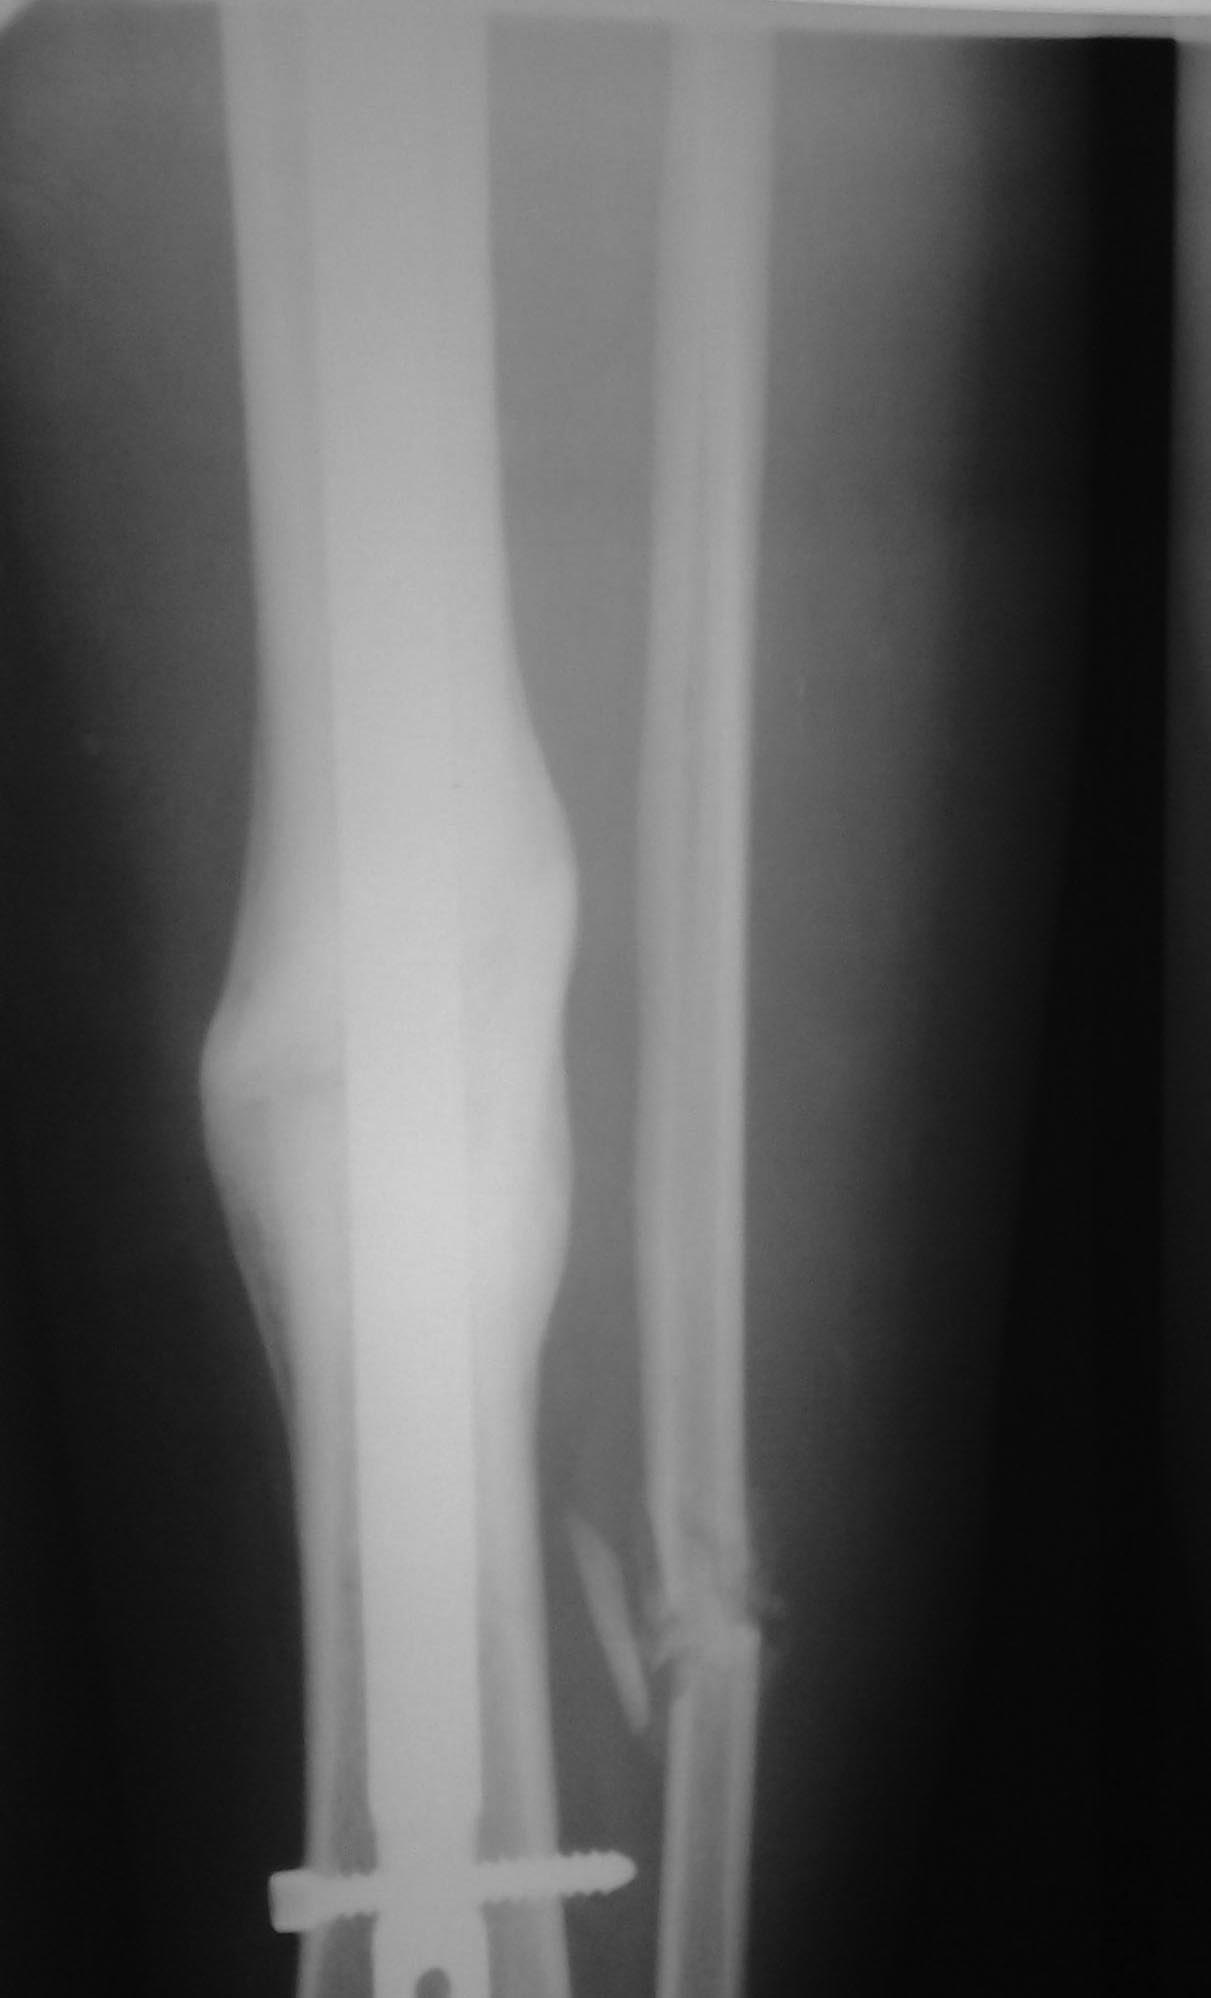

ложный сустав после БИОС б/берцовой кости |

27 Июнь 2013, 23:25 перелом б/берцоовой кости 9 мес назад, 1,5 мес в ЧКДА, после БИОС, остеотомия м/берцовой не выполнялась, сейчас рентгенологически ложный сустав, клинически больную ничего не беспокоит. планируется остеотомия н/3 м/берцовой кости и полная нагрузка на ногу. стоит ли перештифтовать или имеются другие мнения. пациент молодая девушка 25 лет. Я все же выполнил остеотомию м/берцовой кости 1 мес. назад и получил ожидаемый результат – полная перестройка зоны ложного сустава рентгенологически. http://weborto.net/forum/pics/2013/06/2724 http://weborto.net/forum/pics/2013/06/3030